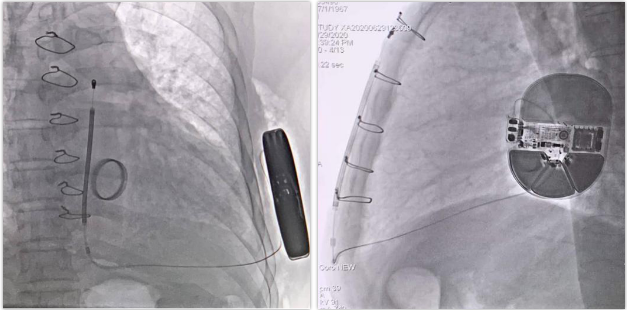

术后影像

本手术采用最新的肌间囊袋植入法,脉冲发生器紧贴肋骨;除颤电极线圈紧贴胸骨柄,贴壁完美,上隧道制作手法与电极固定堪称教学典范;以上两点均保证除颤阈值会更低,术后做PRAETORIAN评分,评分<90,无(低)DFT风险。该手术为第一批3501抗核磁电极植入,为患者保驾护航同时,提供后期核磁检测需求。